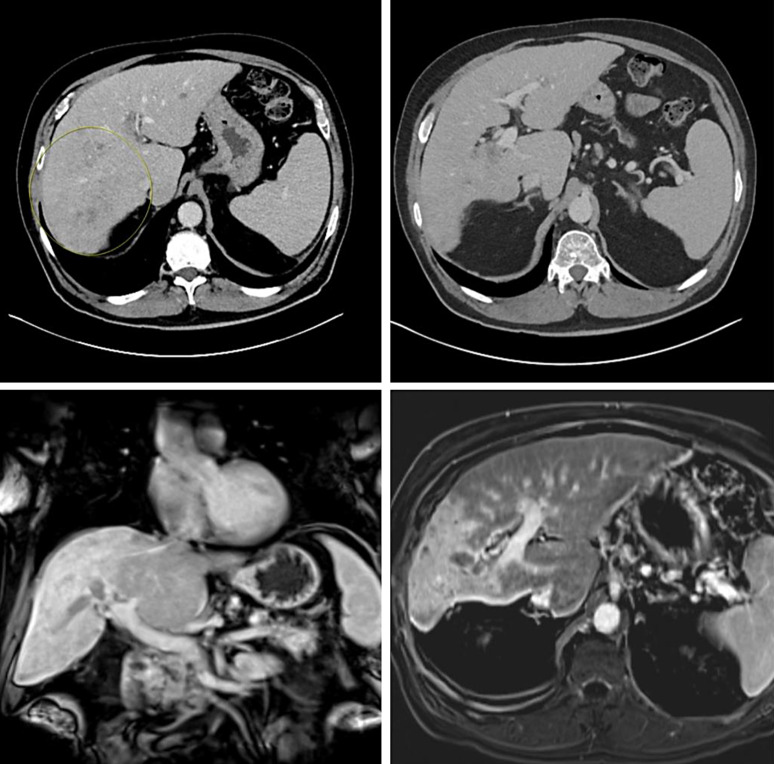

Case report: A 66-year-old male with advanced cirrhosis, hepatitis C, and a history of alcohol use developed HCC, with an AFP level increasing from 3.4 to 3,199. Imaging revealed a 10.7 cm infiltrative mass with portal vein thrombosis, and the patient was diagnosed with Barcelona Liver Clinic (BCLC) stage C HCC. First-line treatment with atezolizumab + bevacizumab was initiated, but the patient did not tolerate the regimen well, leading to discontinuation. He was switched to the STRIDE regimen, which he tolerated well. After six cycles of durvalumab, significant clinical improvement was noted and a follow-up MRI showed reduced tumor thrombus size, and AFP levels dropped significantly to 2, indicating a sustained or improved therapeutic response.